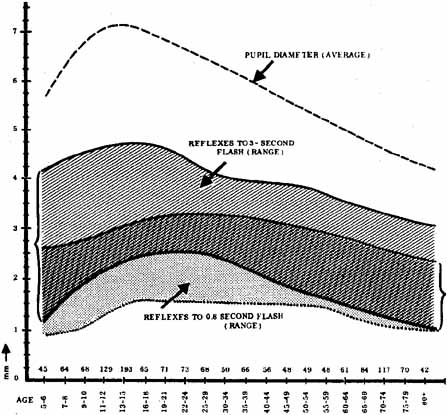

1. Loewenfeld IE: The Pupil: Anatomy, Physiology and Clinical Applications. Boston: Butterworth Heinemann, 1999 2. Wilhelm J, Wilhelm H, Moro S, Barbur JL: Pupil response components: Studies in patients with Parinaud's syndrome. Brain 125(10):2296, 2002 3. Bergamin O, Schoetzau A, Sugimoto K, Zulauf M: The influence of iris color on the pupillary light reflex. Graefes Arch Clin Exp Ophthalmol 236(8):567–570, 1998 4. Thompson HS, Franceschetti AT, Thompson PM: Hippus, semantic and historic considerations of the word. Am J Ophthalmol 71:1116, 1971 5. Loewenfeld IE: Pupillary changes related to age. In Thompson HS (ed): Topics in Neuro-ophthalmology. Baltimore: Williams & Wilkins, 1979:124–150 6. Bourne PR, Smith SA, Smith SE: Dynamics of the light reflex and the influence of age on the human pupil